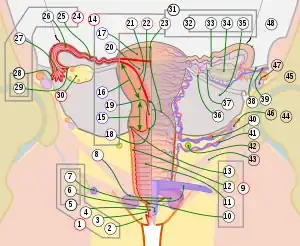

Image showing numbered parts of the fallopian tubes and surrounding structures

Image showing numbered parts of the fallopian tubes and surrounding structures Female reproductive system numbered parts